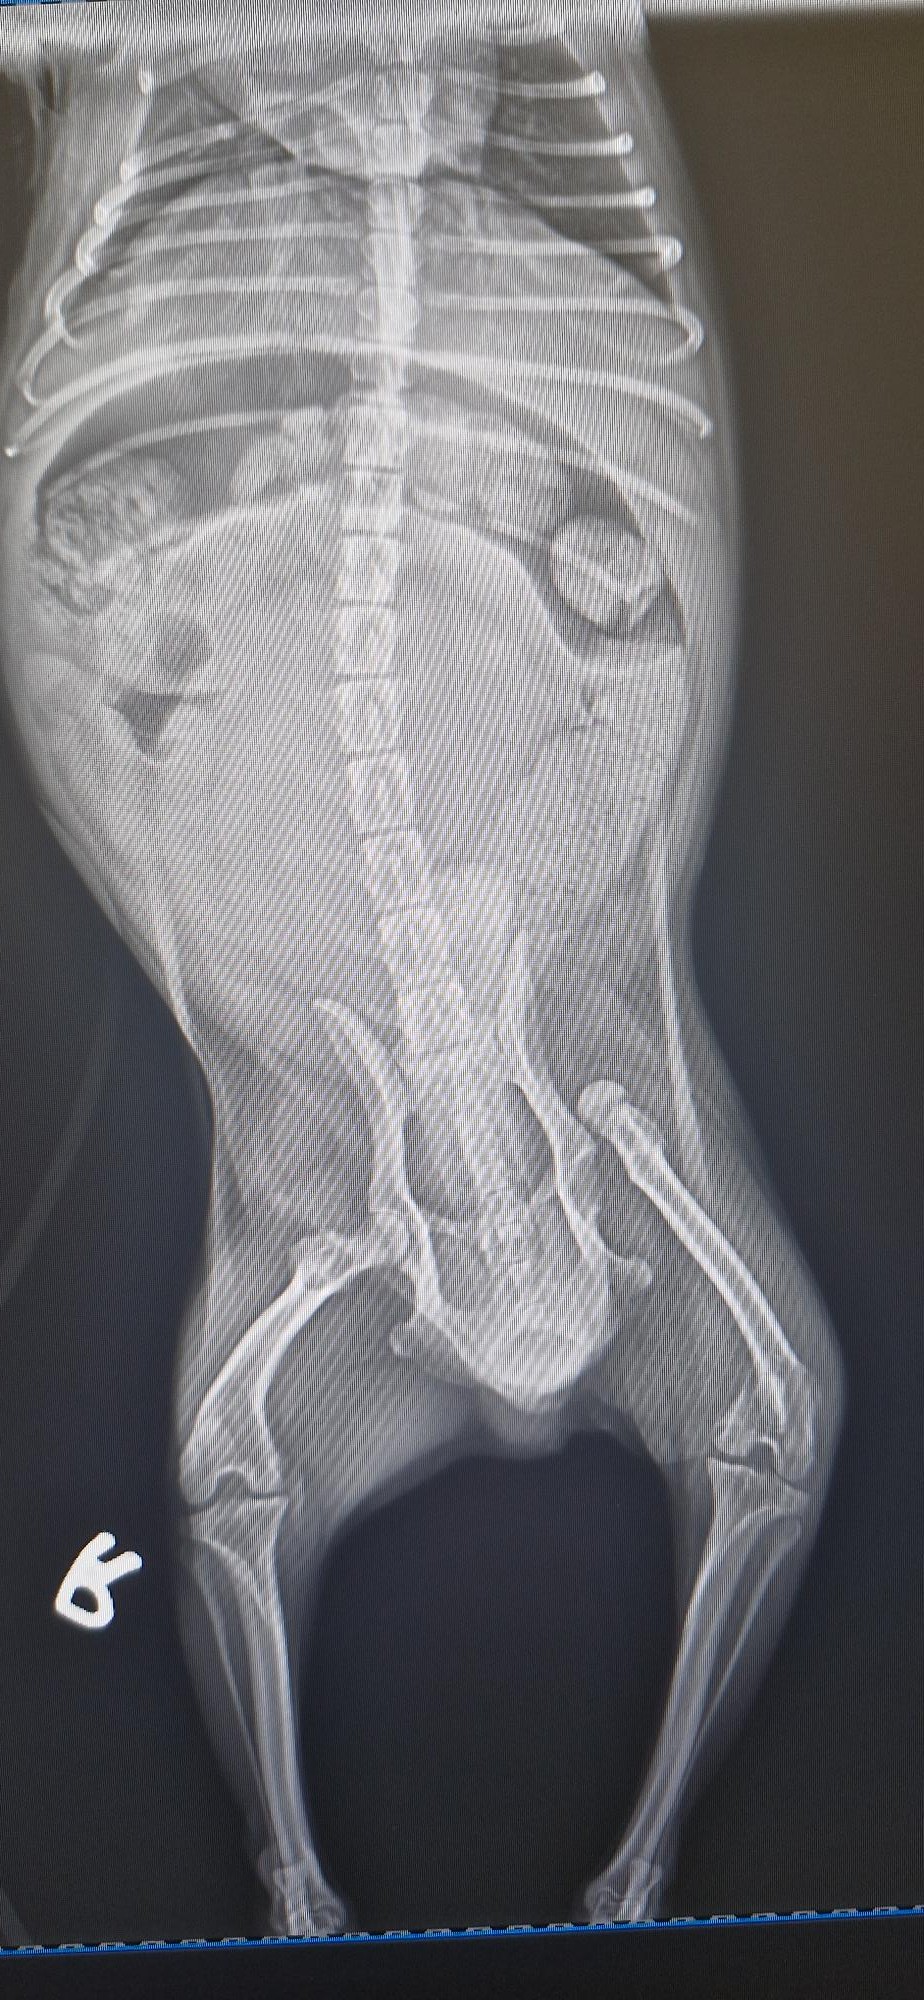

Um lindo Pastor Alemão chamado Max partiu a pata traseira em vários sítios, e a operação para a reparar custaria 1400 euros. O veterinário pediu-nos ajuda, pois o dono não conseguia pagar. Pagámos 700 euros pela operação, e esperamos que fique como novo.

Max

Raio-X do Max